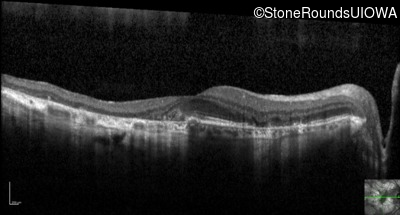

Optical Coherence Tomography - Left - 20/40 +2

Exemplar / OCT Stack

OCT Stack